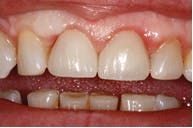

Figure 3: Seven-days post-op

Figure 4: 30-days post-op

Figure 5: Complete with e.max crowns

Solea's precision and ability to maintain a clean surgical site allowed this unscheduled procedure to be completed successfully. Additionally, rapid healing was observed (figure 3). With Solea, this was a minimally invasive procedure and crowns were prepared 30 days postoperatively (figure 5). Traditional surgery would require six to eight weeks until proper conditions were established for definitive restorative work. In addition, there would have been more postoperative pain and slower healing with traditional instruments.